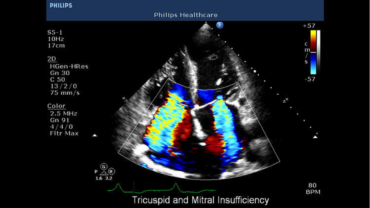

Per intervenire rapidamente è necessario un sistema ecografico portatile Non è semplice riuscire a ottenere dati diagnostici da esami effettuati con sistemi portatili. Con CX50 ora potrete avere ovunque la qualità necessaria per formulare diagnosi affidabili. È il sistema ecografico stesso ad andare dal paziente e può essere trasportato anche in sala operatoria, unità coronarica, unità di terapia intensiva, anche neonatale o pediatrica, presso ambulatori di screening o al pronto soccorso. La qualità delle immagini di CX50 lo rende ideale per i pazienti in condizioni critiche, quando lo spazio è limitato dalla presenza di molte apparecchiature e servono risposte rapide.